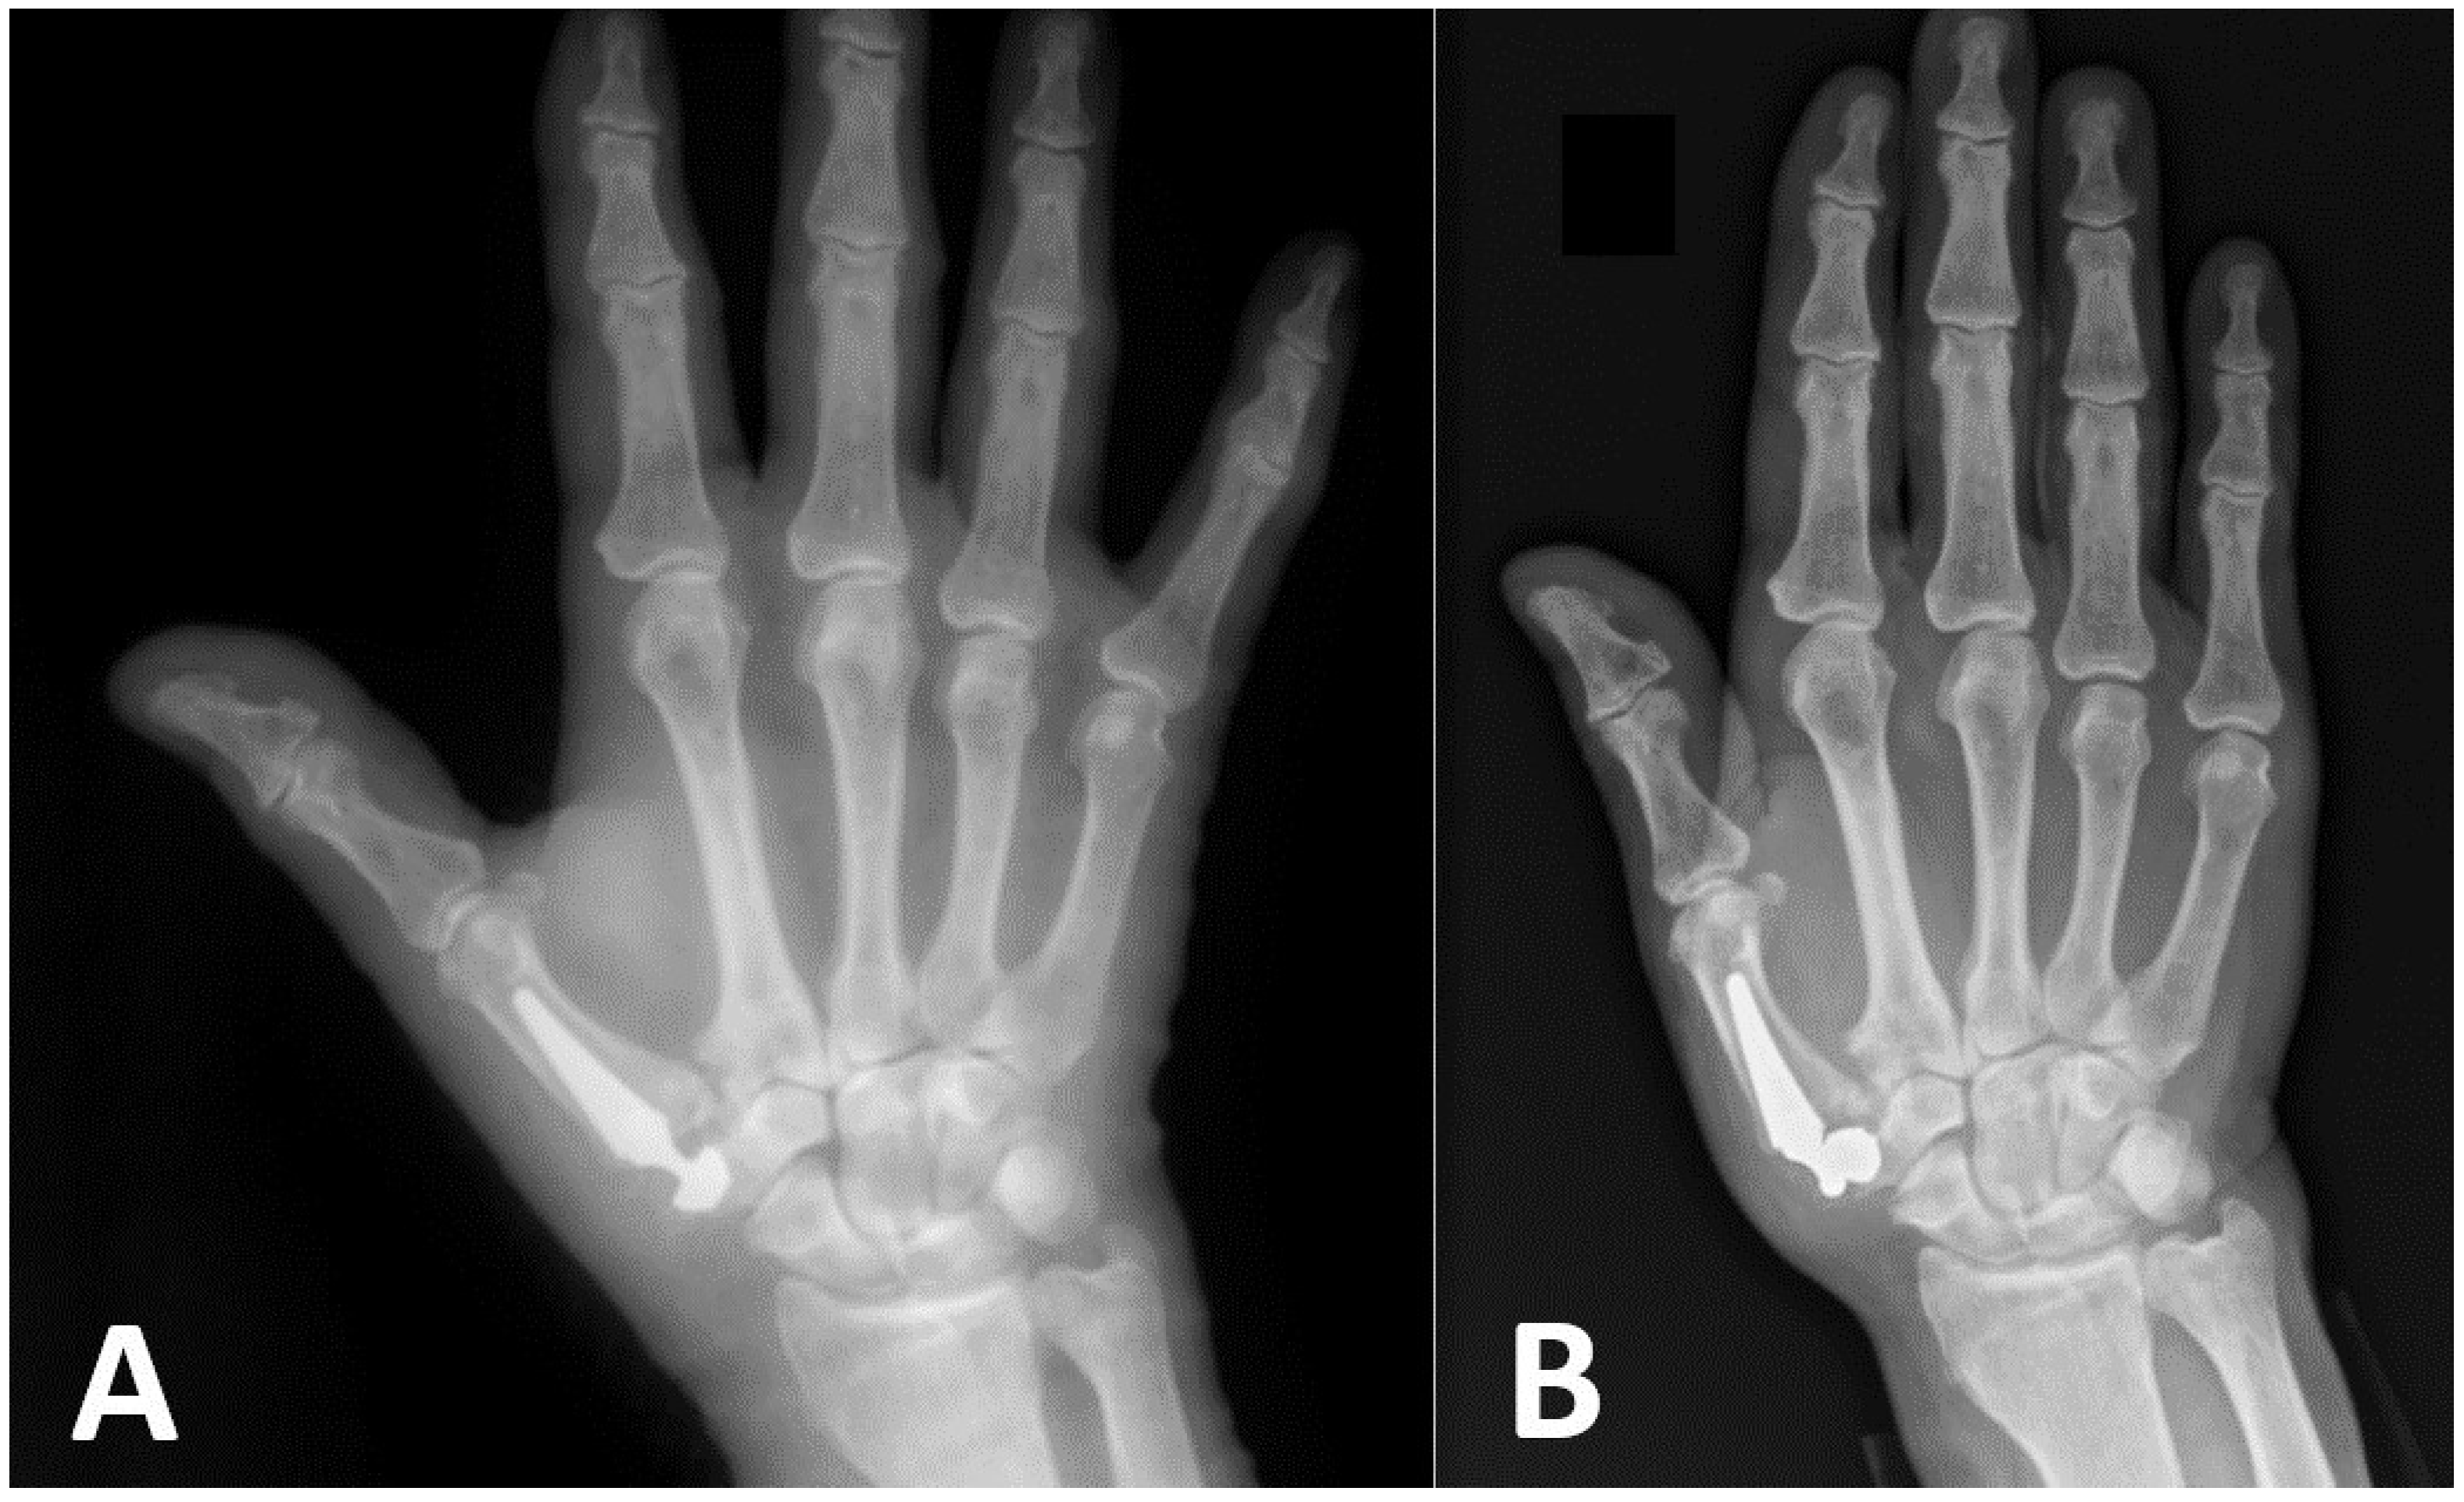

Implant loosening without a fracture may occur early following surgery because of an inability to achieve primary press fit fixation. Careful evaluation of radiographs to assess bone quality, the presence of cysts, and adequate trapezium height are essential steps in preoperative planning. Central cup placement [18], as well as preservation of the hard subchondral bone of the trapezium articular surface, may result in better mechanical fixation of the cup [19]. In four cases in our series, early loosening of an implant’s cup was diagnosed within several weeks following initial surgery, and all of them involved Touch® prostheses. A typical case of such a complication is presented in Figure 2, where immediate post-operative X-rays demonstrated a cup positioned radially and dorsally to the center of the trapezium and early loosening of the cup with dislocation of the prosthesis 2 weeks post-surgery. The Touch® implant has two cup designs. The conus cup is based on the concept that the axial forces maintain its press fit into the trapezium [14]. The hemispheric cup is similar to acetabular cups, and its force distributions may differ. Our results did not show any superiority of one design over the other, as two of the cups which failed were spherical and two were conical. In one case, deepening the cavity in the trapezium was sufficient for stabilizing the cup during revision surgery. In another case, a bone graft from the iliac crest was used to build the bone stock into which a cup was later implanted. In two cases, however, the surgeon was unable to stabilize a cup, and therefore, trapeziectomies were performed. We encountered one case of late loosening of the cup in our series, where the patient complained of new onset pain one year following hemispheric Touch® JR surgery and underwent successful revision surgery with the insertion of a larger cup.

Figure 2.

Immediate (A) and two-weeks’ (B) post-operative X-rays showing early cup loosening and dislocation of the prosthesis.